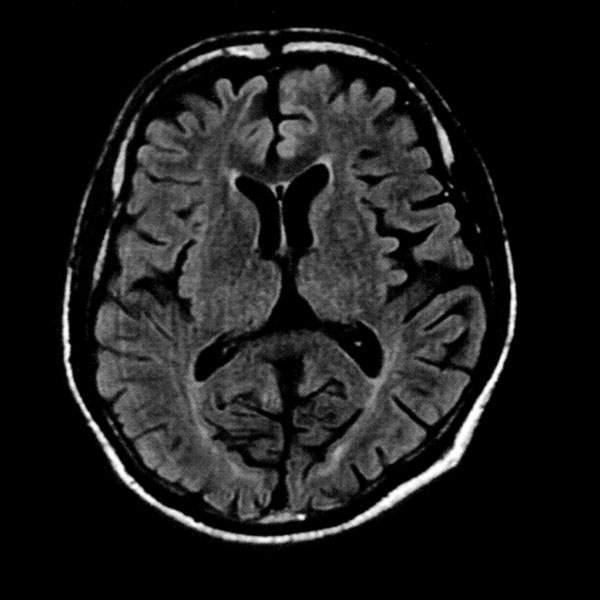

MRI検査

2025年9月16日スタート!!1.5T MRI SIGNA Creator(GE社製)

新しいMRI装置では従来の装置と比較し、高画質、かつ短時間での検査が可能となります。

- AI 機能を搭載:従来の装置と比べかなりの高画質が期待できます

- 従来の装置では難しかった微細な変化の描出にも期待がもてます